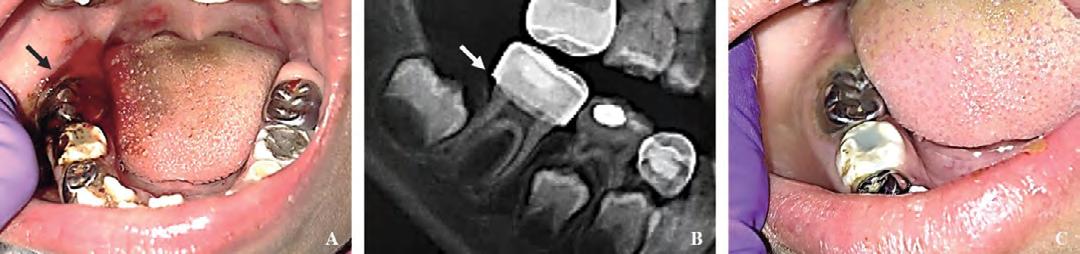

A large liver-like clot was removed in order to perform a clinical examination and ice water-soaked gauze was placed on the site with gentle pressure without improvement. Extraoral evaluation was not significant. Removal of the gauze revealed continuous oozing of heme localized to the gingival sulcus of the mandibular right permanent first molar (Figure 1A), which had a PMC placed one day prior. The radiograph (Figure 1B) revealed normal dental development for chronological age, multiple restorations on the permanent and primary dentition, and no radiographic radiolucency indicating signs of pathology. Proximity was noted on the distal margin of the PMC on the mandibular right permanent first molar to the adjacent tooth follicle.

Local anesthetic infiltration in the form of 2% lidocaine with 1:100,000 epinephrine was administered surrounding the affected area, and the gingival sulcus was curetted and irrigated with saline solution to remove any local irritants. The gingival sulcus was packed with a gelatin matrix and the gingival tissues cauterized. Hemostasis was achieved, and the patient was instructed to provide continuous biting pressure (Figure 1C). The patient was discharged and received follow-up care in the outpatient dental clinic the next day, at which time she was exhibiting absence of bleeding complications and normal healing gingival tissues.

lary left permanent first molar region (Figure 2A). Figure 1: (A) Bleeding localized to lower right quadrant, from distal segment (black arrow) of gingival sulcus of lower right permanent first molar, post-removal of currant jelly-like clot. (B) Imaging revealed intact restorations and no radiolucencies or pathology. Close proximity of distal margin of preformed metal crown on lower right permanent first molar to dental follicle of lower right permanent second molar was noted (white arrow). (C) Area surrounding lower right permanent first molar with hemostasis achieved using local hemostatic measures.